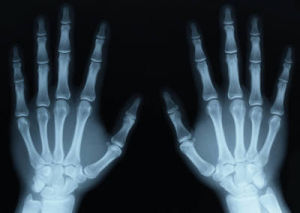

手部x光片 1895年11月8日傍晚,他研究陰極射線。為了防止外界光線對放電管的影響,也為了不使管內的可見光漏出管外,他把房間全部弄黑,還用黑色硬紙給放電管做了個封套。為了檢查封套是否漏光,他給放電管接上電源(茹科夫線圈的電極),他看到封套沒有漏光而滿意。可是當他切斷電源後,卻意外地發現一米以外的一個小工作檯上有閃光,閃光是從一塊螢光屏上發出的。然而陰極射線只能在空氣中進行幾個厘米,這是別人和他自己的實驗早已證實的結論。於是他重複剛才的實驗,把屏一步步地移遠,直到2米以外仍可見到屏上有螢光。倫琴認為這不是陰極射線了。倫琴經過反覆實驗,確信這是種尚未為人所知的新射線,便取名為X射線。他發現X射線可穿透千頁書、2~3厘米厚的木板、幾厘米厚的硬橡皮、15毫米厚的鋁板等等。可是1.5毫米的鉛板幾乎就完全把X射線擋住了。他偶然發現X射線可以穿透肌肉照出手骨輪廓,於是有一次他夫人到實驗室來看他時,他請她把手放在用黑紙包嚴的照相底片上,然後用X射線對準照射15分鐘,顯影后,底片上清晰地呈現出他夫人的手骨像,手指上的結婚戒指也很清楚。這是一張具有歷史意義的照片,它表明了人類可藉助X射線,隔著皮肉去透視骨骼。1895年12月28日倫琴向維爾茨堡物理醫學學會遞交了第一篇X射線的論文“一種新射線——初步報告”,報告中敘述了實驗的裝置,做法,初步發現的X射線的性質等等。X射線的發現,又很快地導致了一項新發現——放射性的發現。